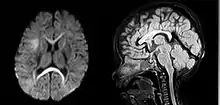

An MRI of a patient with benign familial macrocephaly (male with head circumference > 60 cm)